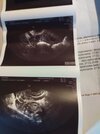

Mam problem, nie wiem co robić. Ostatnio miałam 27 grudnia miesiączkę i do tej pory nie miałam . Wyszło mi 5 testów pozytywnych , poszłam w poniedziałek do ginekolog się on nie widział żadnej ciąży natomiast robił mi cytologię i badanie macicy. A wczoraj tak źle się czułam że brzuch mnie bolał i krwawiłam i do tej pory krwawię. Robiłam na sorze wczoraj badanie HCG kombo i wyszło że jestem w ciąży ale strasznie małe tylko 19.6 a lekarz mówił żebym przyszła w poniedziałek na powtórne badanie krwi . Obliczyli że jestem w 4 tygodniu i 4 dzień . Nie wiem co robić . Pierwszy raz mam coś takiego.

A jeśli będzie tak samo? .może się orientujesz co na tym zdjęciu widać

Najprawdopodobniej beta spada i poronienie.

Ale trzeba sprawdzić, czy beta nie rośnie, bo wtedy ryzyko ciąża pozamacicznej.